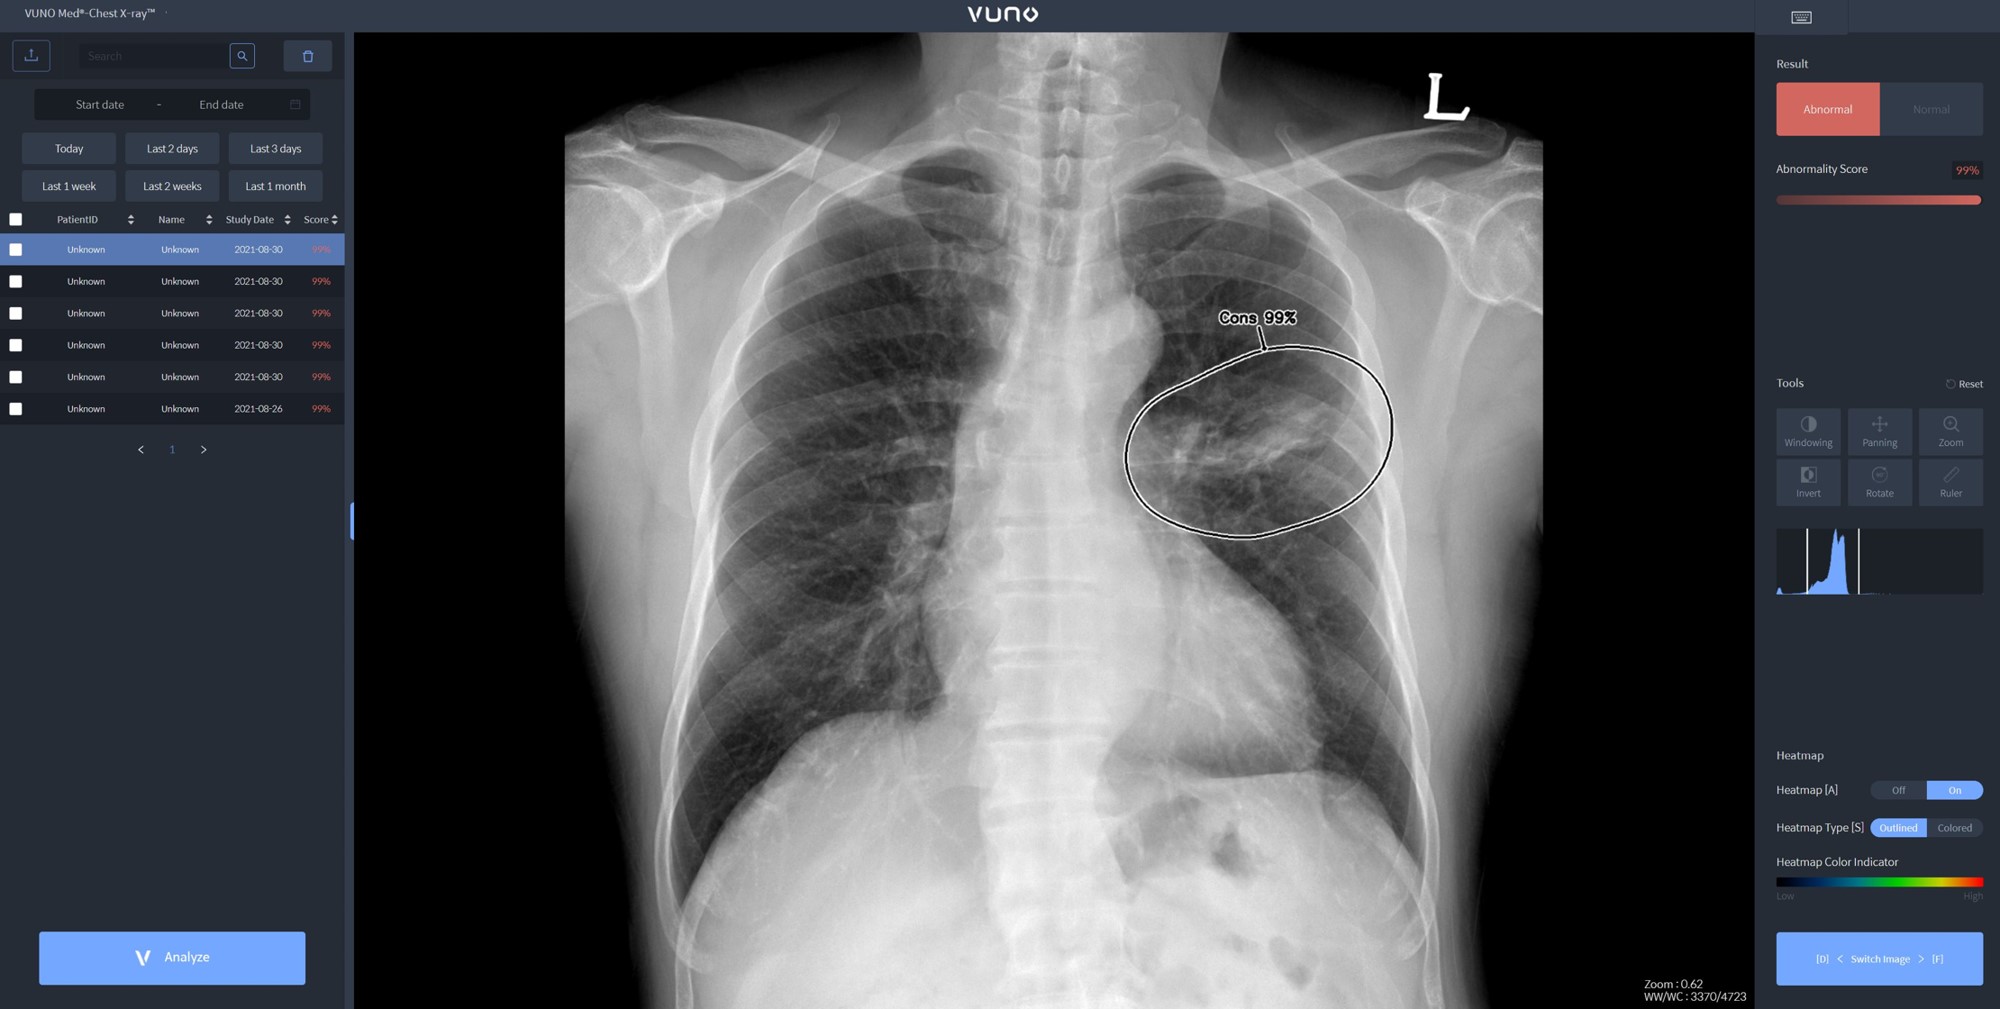

자이드 군 병원에 도입된 솔루션은 이동형 엑스레이 장비에 뷰노 AI 기반 흉부 엑스레이 판독 보조 솔루션 뷰노메드 체스트 엑스레이™(VUNO Med®-Chest X-ray™)를 탑재한 패키지 제품이다. 별도 차폐 시설 없이 다양한 상황에서도 쉽게 환자 흉부 엑스레이 촬영을 할 수 있는 이동형 장비에 인공지능을 연동해 수 초 이내 판독 결과를 확인할 수 있다.

한편, 뷰노메드 체스트 엑스레이™는 흉부 엑스레이 영상에서 결절, 경화, 간질성 음영, 흉수, 기흉 등 주요 이상 소견을 높은 정확도로 탐지하는 인공지능 솔루션이다. 의료진에게 이상소견명과 위치를 제시해 결핵, 폐렴 등 주요 폐 질환 진단을 돕는다.